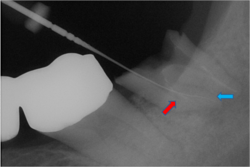

根のカーブに対応できず間違った方向へ削り込んでしまっています(赤矢印)

古い薬を除去しとあるテクニックを駆使し正しい根幹への道を見つけました(青矢印)

簡単にやっているように見えますがそのまま器具を入れては大きく間違った道に導かれてしまうなか、その脇から1mmにも満たない狭く曲がった孔を探しそちらへ導くのは至難の技ですが、マイクロスコープとCTを使いしっかりとした手法で行うとこのような症例にも対応できます